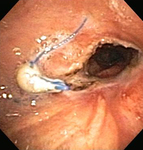

Post-lung transplant anastomotic bronchial stenosis: electrocautery radial incision

From the collections of Jose Fernando Santacruz MD, FCCP, DAABIP and Erik Folch MD, MSc; used with permission